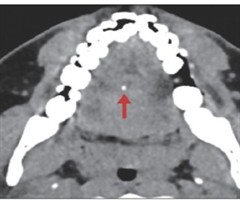

经舌腹入路取出舌根内鱼刺异物1例

[摘要]舌内异物在临床上较为罕见,其精确定位和适宜的手术路径选择对于降低手术风险和减少术后并发症至关重要。本文报道1例在影像学精确定位辅助下经舌腹入路取出舌根鱼刺异物的病例。...